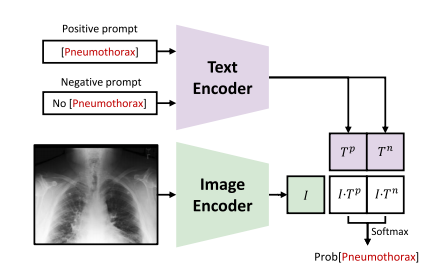

Fig. 10. Illustration of the positive/negative prompt engineering for zero-shot diseasediagnosis. The diagnosis of Pneumothorax is demonstrated here, while other potentialdiseases can also be diagnosed in this way

图10:用于零样本疾病诊断的正/负提示工程图示。此处展示了气胸的诊断过程,其他潜在疾病也可以通过这种方式进行诊断。